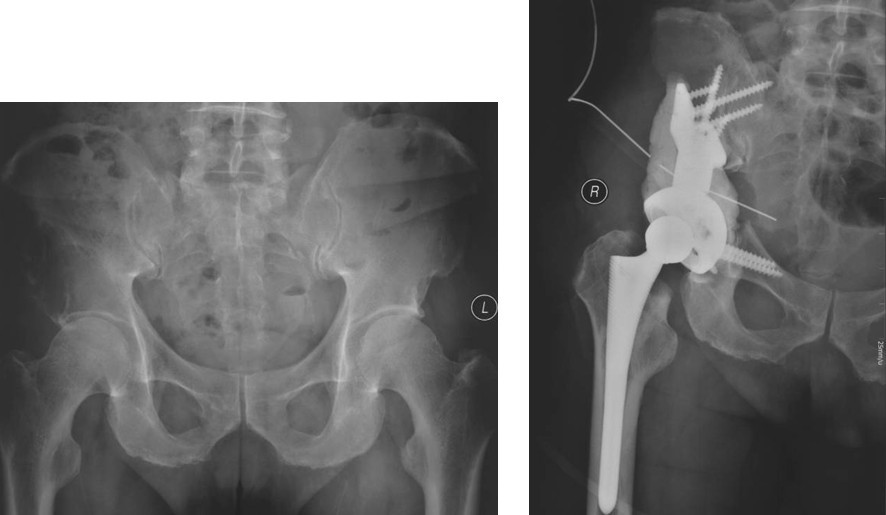

图2,女,31岁,乳腺癌髋臼转移, Harrington I型

Ⅰ型:髋臼外侧皮质,上方及内侧壁完好,髋臼下及前后方破坏缺损。可以采用骨水泥固定的普通全髋置换术以达到长期牢固固定。手术入路一般采用后外侧入路,不需要大转子截骨,可在髋臼深部放置金属网以加强骨水泥的固定效果,阻挡股骨头向内移位。术后第一天病人即可在耐受范围内下地活动并完全负重。